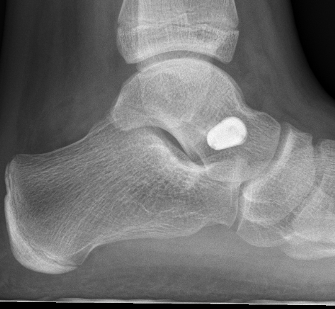

Subtalar arthroeresis

implantimplantimplant

Concept

Sinus tarsi implants limit excessive pronation

Endosinotarsal - implant in the sinus tarsi

Exosinotarsal - screw external to the sinus tarsi